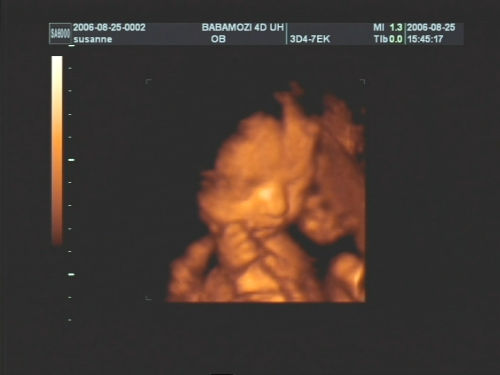

Pár kép:)

És akkor jöjjenek a képek:

Nem tudtam betelni velük,és nem tudtam választani közülük,azért van ilyen sok:

Kép Olyan kis szégyellős volt a drága,hogy állandóan takargatta a szemeit:Kép